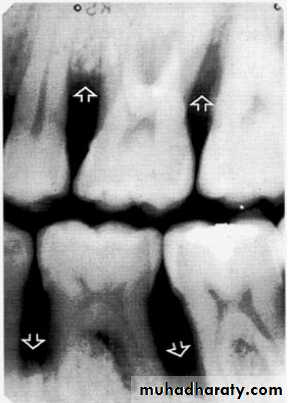

Bone loss

• Severity: classified to

Mild bone loss: crestal changes (The anterior regions show blunting of the alveolar crests and slight loss of alveolar bone height.Posteriorly show loss of the normally sharp angle between the lamina dura and alveolar crest).

• Moderate bone loss: bone loss of 10-33%.

• Severe bone loss: bone loss of 33% or more.

Mild bone loss